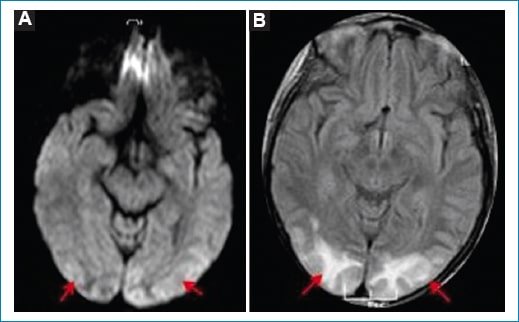

• Hallazgos típicos: áreas con edema vasogénico caracterizadas por hiperintensidad en T2 y FLAIR e hipointensidad en T1 a nivel parieto-occipital bilateral. La difusión suele ser negativa, ya que se debe a edema vasogénico (Fig. 1). Sin embargo, cuando no se realiza un diagnóstico precoz puede evolucionar a edema citotóxico (irreversible), en cuyo caso dichas áreas presentan restricción en difusión con caída de señal en el mapa de ADC, o puede asociarse a la existencia de hemorragia subaracnoidea (HSA)1,4.

Figura 1. Eclampsia. Cortes axiales de RM en secuencia potenciada para FLAIR (A y C) y T2 (B y D). Se observan áreas hiperintensas cortico-subcorticales parieto-occipitales bilaterales y simétricas (flechas).